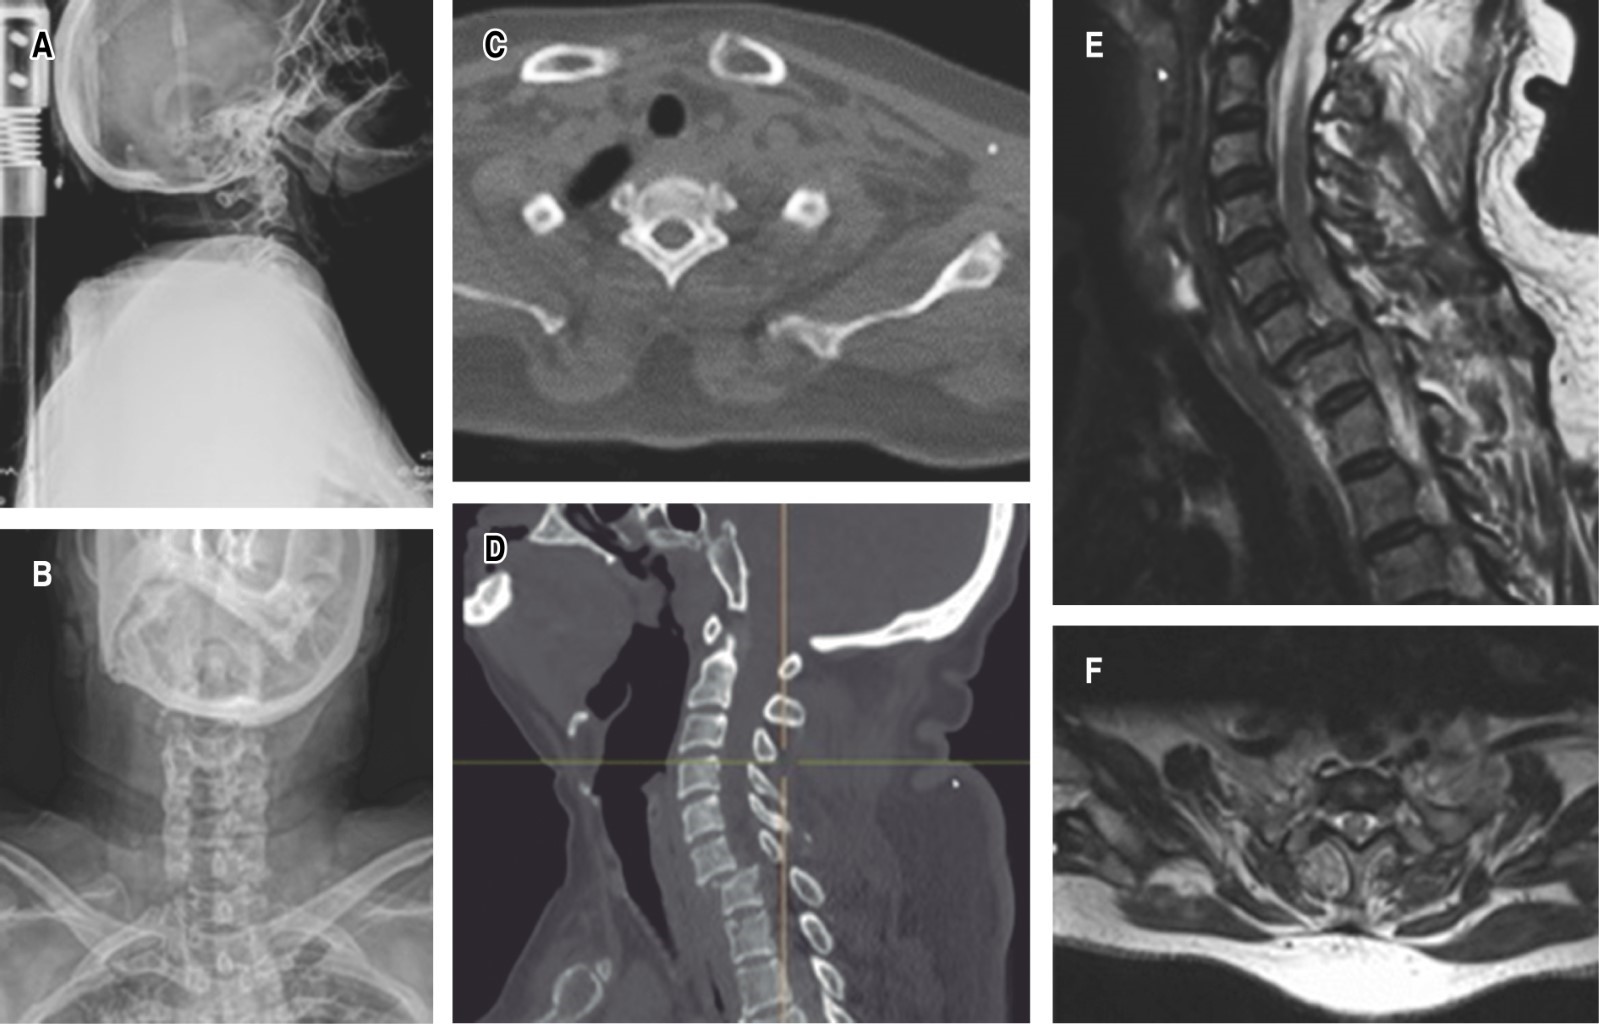

Ingresa para tratamiento quirúrgico de urgencia en medio particular el 02/11/2021, dentro de las primeras 24 horas posteriores a la lesión, con doble abordaje en un solo tiempo quirúrgico y se inicia con un abordaje cervical posterior para la estabilización a masas laterales C3 a C6 (masa lateral C6 izquierda, al momento de la cirugía se observa fracturada y no realiza estabilización en dicha región) con laminectomía C5-C6 y artrodesis posterolateral. Se procede a colocar al paciente en de cubito supino para continuar con un abordaje cervical anterior, se realiza corpectomía C5, colocación de malla de titanio en C5 y placa cervical anterior C4-C6, con tiempo quirúrgico total de tres horas 30 minutos y un sangrado de 300 mililitros (Figura 6).